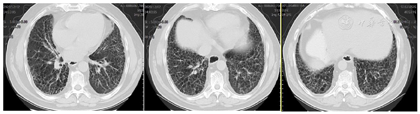

患者经治疗后肿瘤病灶明显缩小(图3,图4,图5,图6,图7,图8),定期于我院随访复查,目前一般情况良好,未见复发及远处转移。

PD-L1是一种跨膜糖蛋白,属于B7家族成员之一,一级结构包括290个氨基酸,亦由胞外区、疏水跨膜及尾部胞浆区组成[2]。有研究发现,PD-L1蛋白广泛表达于活化T淋巴细胞、巨噬细胞、B细胞等免疫细胞,还表达于多种类型的恶性肿瘤细胞表面,比如乳腺癌、胶质瘤、恶性黑色素瘤等[3]。PD-L1与其受体程序性死亡分子1 (PD-1)结合形成PD-1/PD-L1通路,该通路可介导形成机体的免疫抑制微环境,参与肿瘤细胞的免疫逃逸,继而促进肿瘤的发展。研究发现,27%~50%的肺癌患者可表达PD-L1[4,5],Koh等人[6]发现,在肺腺癌组织中PD-L1的阳性表达率为59%,且其阳性表达与患者淋巴结转移、组织分化程度及吸烟有关。有研究结果表明,肺鳞癌组织PD-L1阳性表达明显高于正常肺组织,PD-L1阳性表达与患者pTNM分期、淋巴转移有关,提示PD-L1在肺鳞癌的发生、进展过程中具有重要作用[3]。但目前单独研究PD-L1对肺鳞癌患者预后影响的报道甚少,尤其是伴有肺间质纤维化的肺鳞癌患者的相关研究更少,有待于大规模的临床试验。PD-L1抑制剂虽然可以达到预期的抗肿瘤效果,但这是一个非常复杂的过程,也有发生免疫相关不良事件的风险,包括诱发各种器官的炎症反应[7,8]。目前,其背后的机制仍不清楚,但先前的肺部疾病可能是免疫检查点抑制剂诱发肺炎的一个危险因素[9],所以由于肺炎的风险增加,肺间质纤维化合并肺癌患者接受免疫检查点抑制剂治疗的报道甚少。在以往的研究中,与传统非小细胞肺癌的化疗方案相比,抗PD-1治疗导致重度免疫相关性肺炎的发生率较高,但抗PD-L1治疗则不然[10]。也有研究显示,使用PD-1抑制剂患者3/4级免疫相关性肺炎的发生率仅略高于使用PD-L1抑制剂的患者[11]。此例病人为肺鳞状细胞癌伴肺间质纤维化,肿瘤细胞的PD-L1阳性表达百分比高达78%,因此在GP方案化疗的同时联合应用PD-L1抑制剂度伐利尤单抗,并在化疗与免疫联合治疗5疗程后以度伐利尤单抗单药维持。复查时可见右肺下叶的肿瘤病灶迅速且明显缩小,肺间质纤维化未见进展。患者治疗初期躯干部有散在皮疹出现,经抗过敏治疗后皮疹消失。患者1年半来复查病情稳定,未见复发及除淋巴结以外的其他部位转移,没有报告过除散在皮疹以外的免疫相关不良事件发生,也进一步证实了肺鳞癌病人化疗联合抗PD-L1药物作为一线治疗方案的可行性和安全性,为临床工作中肺鳞癌病人的治疗提供了新的思路。但目前病例数少,有待于大规模的临床试验。我们期望,在不远的未来,免疫治疗可使越来越多的肺癌患者获益。